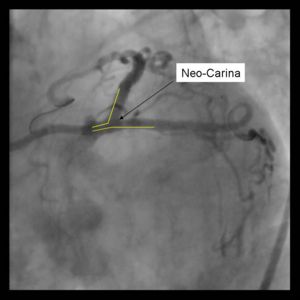

Un-endothelialized layer of stents forming neo-carina may predispose to stent thrombosis. 8Fr Guide system required May be difficult to re-access side branch or parent vessel

3) Both stents are advanced into the side branch and parent vessel. This may require further predilitation. Generally, the stents are advanced beyond the delivery point. Operator preference differs with respect to amount of overlap. Some operators form a long segment of overlap (>5mm), while others try to minimize overlap. It is absolutely essential that both vessels are covered during the balloon inflation. Optimal placement is ensured by advancing both stents distal to the intended deployment site then pulling them back into position. The proximal marker segements should be aligned, with positional confirmation in at least 2 separate views.